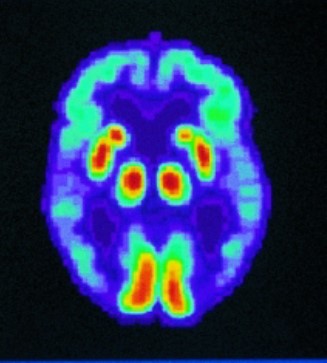

Figure 1 shows the PET Scan of the Normal Brain, and Figure 2 shows the PET Scan of the Alzheimer's Disease Brain.

Figure 2: PET Scan of Alzheimer's Disease Brain [55].

- PET (Positron Emission Tomography): Glucose metabolism in certain areas of the brain is measured.

Inactive areas often overlap with areas associated with Alzheimer's.

In addition, special PET scans are being developed that can directly image amyloid plaques.